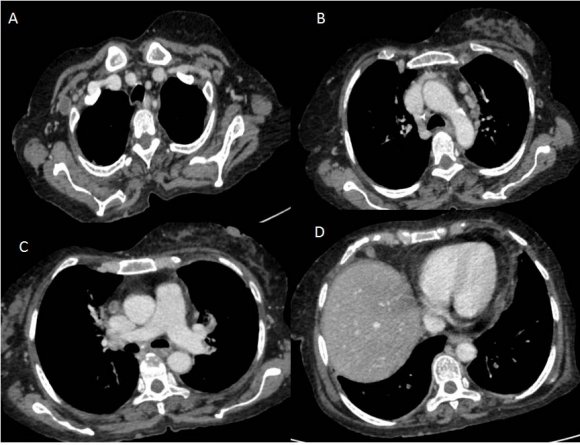

Computed axial tomography (CT scan) of the thorax (Figures: 1-3) showed small patchy areas of alveolar consolidation in the peripheral portion of the right middle lobe and lingula, and the left perihilar region. Multiple small nodular lesions were noted in the peribronchial region in the anterior basal segment of the right lower lobe and segmental bronchi of lingula. Multiple lymph nodes of size 5 to 10 mm were noted in pretracheal, right paratracheal, subcarinal region, in prevascular space and aortopulmonary window. Bilateral axillary lymph nodes also noted, the largest right axillary lymph node measured 13x13mm. Most of the lymph nodes showed peripheral enhancement with central hypodense areas of necrosis. Lymph nodes were also noted in the right juxtadiaphragmatic region, the largest measuring 13x9mm. There was no pleural effusion on either side.

Figure 2. Figure 1 :Figure 2 :

12Figure 1: HRCT of thorax showing patchy areas of alveolar consolidation in the right middle lobe, in lingula (A) and multiple small nodular lesions in the peribronchial region in the anterior basal segment of the right lower lobe.(B)

Figure 3. Figure 3 :

3Figure 3: Contrast-enhanced CT scan of thorax showing lymph nodes in right axilla (A), in prevascular space (B,C), and the right juxtadiaphragmatic region (D) showing peripheral enhancement with central hypodense areas of necrosis.